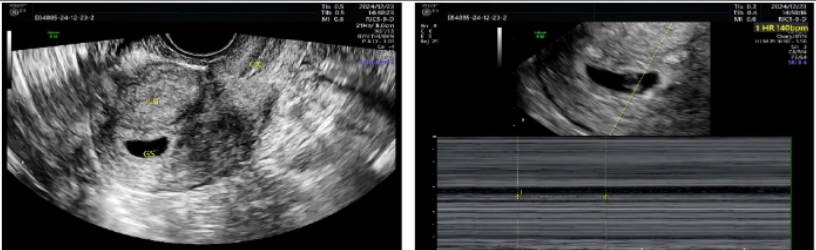

一位处于育龄阶段的女性,其健康状况让人担心。2024年5月24日,是她最后一次来月经的日子。在月经第20天的时候,做了四维彩超,结果显示出不少问题。内膜厚度不均匀,下段大约是2.3mm,中段约为3.1mm,上段约4.7mm。内膜的这种情况不太好,这为后续的诊断以及治疗埋下了隐患。

原来,这位患者在2024年1月的时候,曾在外院做过宫腔镜下宫腔粘连分离术,手术过程中还进行了上环术。然而此次通过四维彩超检查,又发现存在宫腔粘连的可能性,以及宫内节育器下移并嵌顿的可能性。另外,她有剖宫产手术史,由此形成了瘢痕子宫,她在2014年做过剖宫产术,2023年因为脑干胶质瘤出现了特殊情况,不良孕产史给治疗增加了复杂性。

2024年5月15日,患者做了第一次宫腔镜手术,手术中发现宫颈管内口粘连只有小孔,呈现出疤痕化,医生用勺状钳扩张分离后进入了宫腔。2024年7月12日,第二次月经结束,患者再次住院做宫腔镜手术,同样的问题出现了,还是通过勺状钳扩张分离进入宫腔。手术过程虽然明确,但是难度不小。